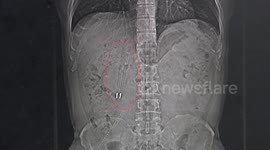

Chinese doctor removes pin from 7-month-old boy's body after he swallowed it

A doctor in southern China removed a pin from a 7-month-old boy’s body after he swallowed it.

The video, captured in the city of Chengdu in Sichuan Province on April 3, shows a doctor named Liu Yinghua using a tool to take a 2-centimetre-long pin out of a baby’s body during surgery.

According to reports, the baby mistakenly swallowed the pin when he was playing.

Fortunately, the pin was removed successfully and the baby has discharged from the hospital after two days of observation.